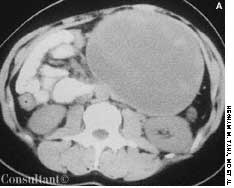

Over the previous 6 months, a 59-year-old man had experienced lethargy, fatigue, poor appetite, cold intolerance, and abdominal distention. His vital signs were normal; physical examination revealed periorbital and pretibial edema, distant heart sounds, and delayed reflexes.